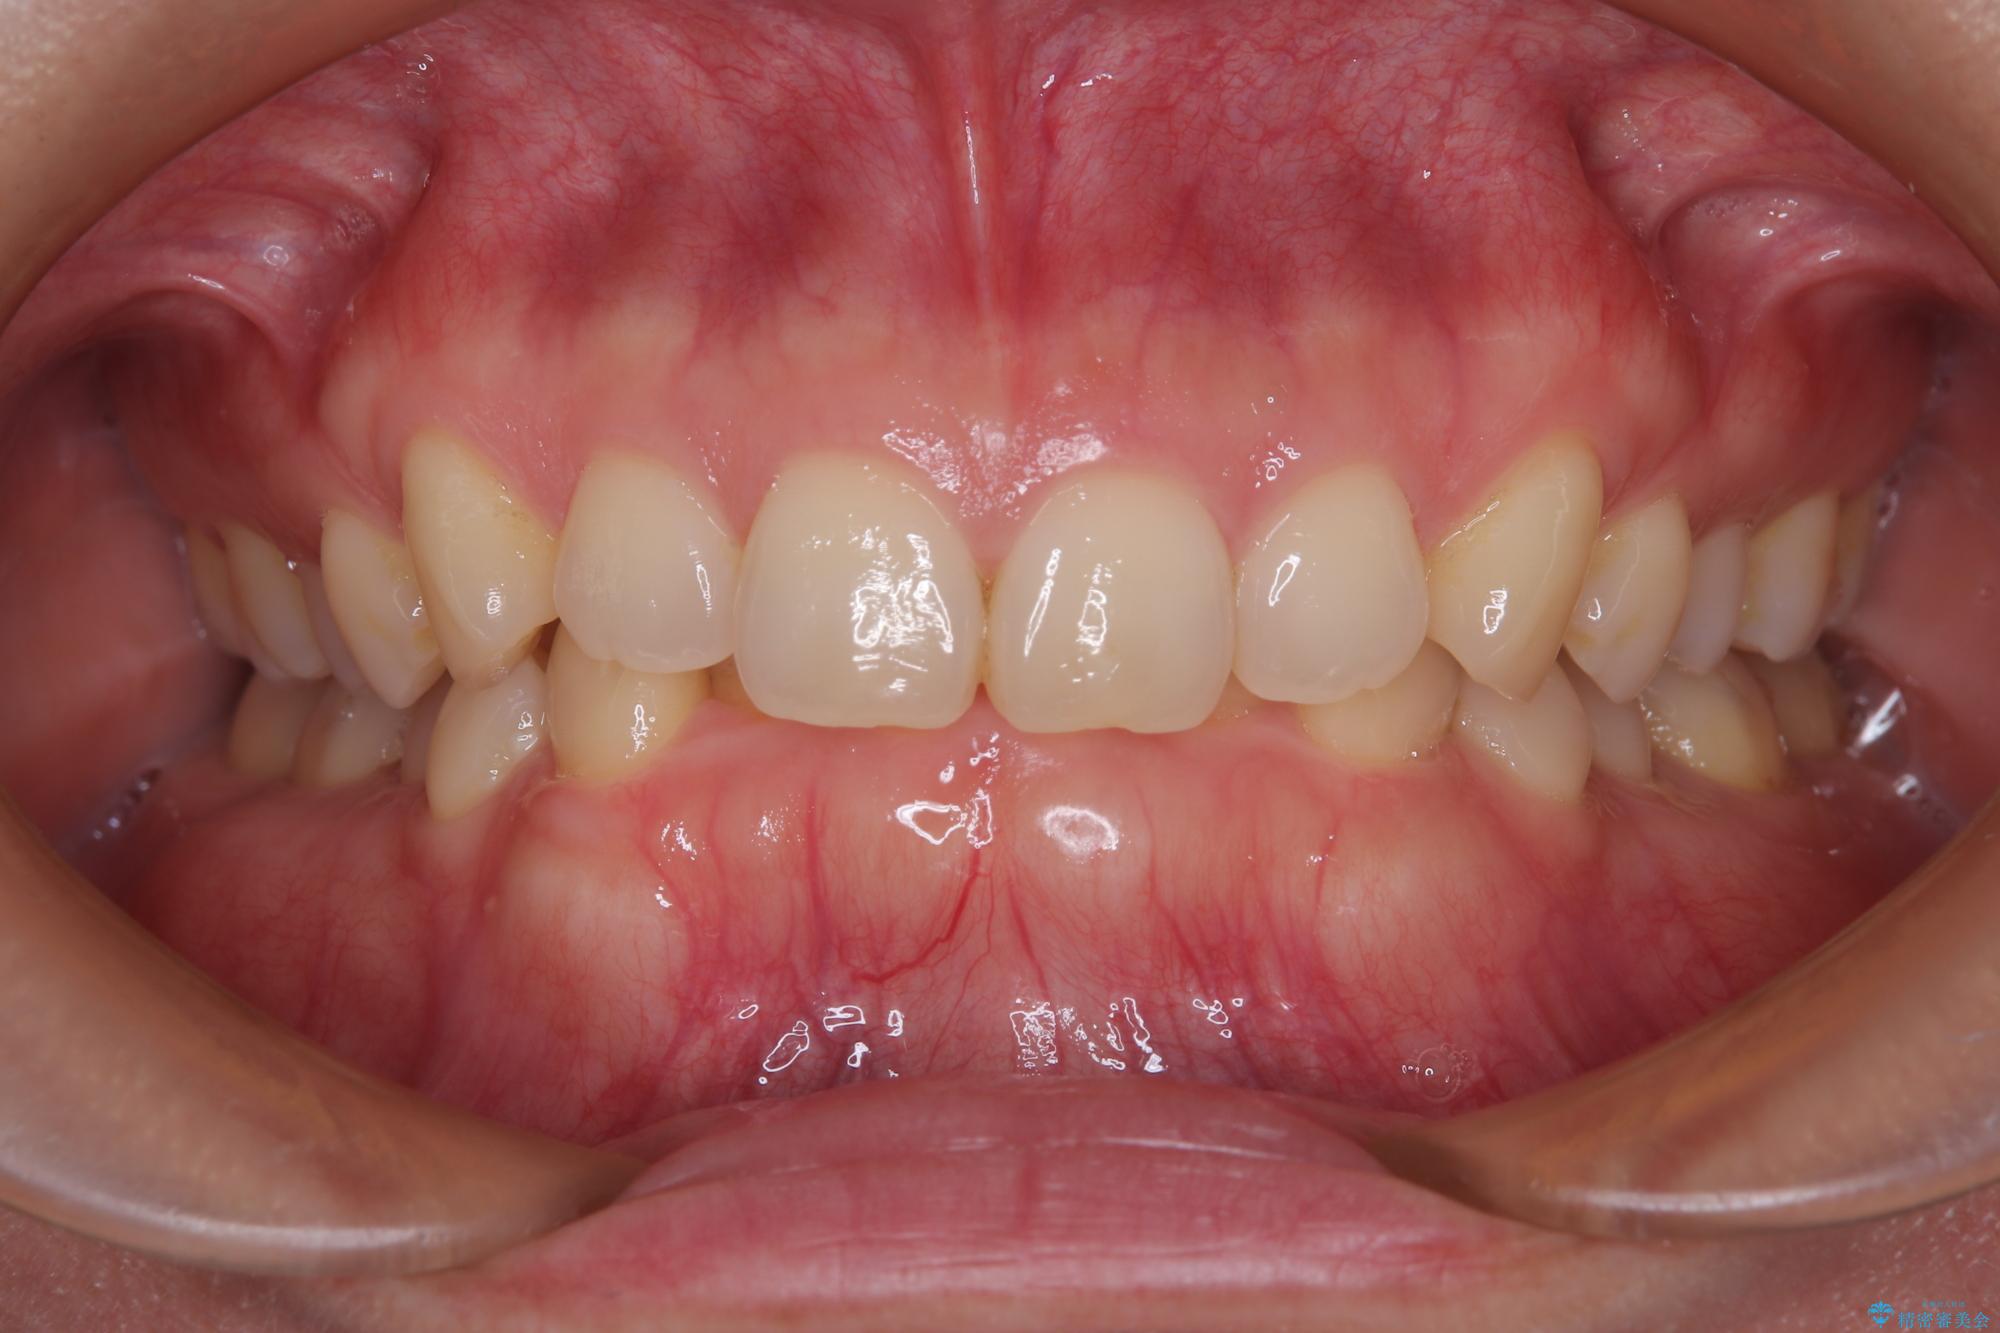

隠れた前歯が気になる ディープバイトのワイヤー矯正治療

- 下顎前歯が完全に隠れてしまっていることを気にして来院された患者様です。

下顎の臼歯が手前に傾斜していることで咬み合わせが深くなってしまい、下顎前歯が見えないほどに上顎前歯が覆い被さっている状態でした。

下顎臼歯を起き上がらせるためにユーティリティーアーチを使用し、一気に深い咬み合わせを改善することができました。